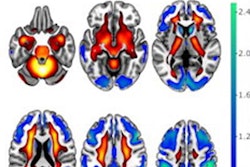

The excitement was palpable in the air of the Metro Toronto Convention Center as we covered the Society of Nuclear Medicine and Molecular Imaging (SNMMI) annual meeting, held June 8-11. Our top story from the meeting was the ever-popular Image of the Year, which went to a team at Yale University for a study that revealed brain nuclei activity with a new research scanner named NeuroExplorer.

- SNMMI: Image of the Year shows early brain nuclei activity